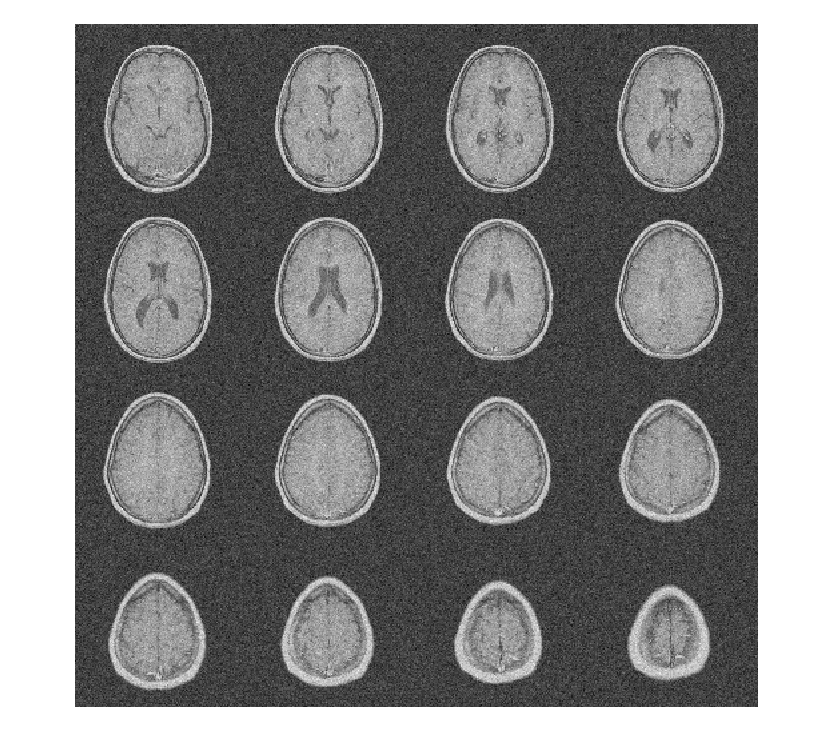

Чтобы продемонстрировать это, рассмотрите набор данных MRI, состоящий из 16 срезов. Гауссов шум со стандартным отклонением 10 был добавлен к исходному набору данных. Отобразите шумный набор данных.

load MRI3D montage(reshape(noisyMRI,[128 128 1 16]),'DisplayRange',[])

Обратите внимание на то, что исходный ОСШ до шумоподавления составляет приблизительно 11 дБ.

ans = 11.2997

Denoise набор данных MRI вниз к уровню 4 с помощью и DTCWT и DWT. Подобные длины фильтра вейвлета используются в обоих случаях. Постройте получившийся ОСШ в зависимости от порога. Отобразите denoised результаты и для DTCWT и для DWT, полученного в лучшем ОСШ.